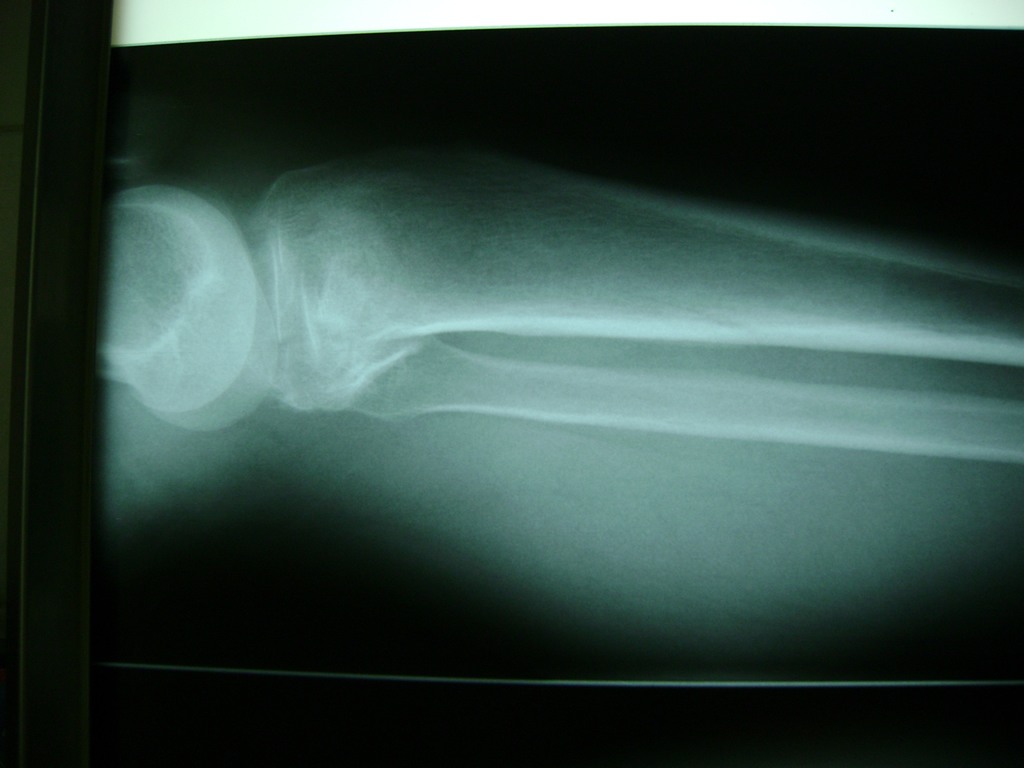

Cirugías de Codo - Rodilla

La artroscopia de rodilla es un cirugía en el cual la estructura interna de la articulación es examinada ya sea para realizar un diagnostico o para realizar un tratamiento, este procedimiento se realiza utilizando un instrumento parecido a un pequeño tubo llamado artroscopio.